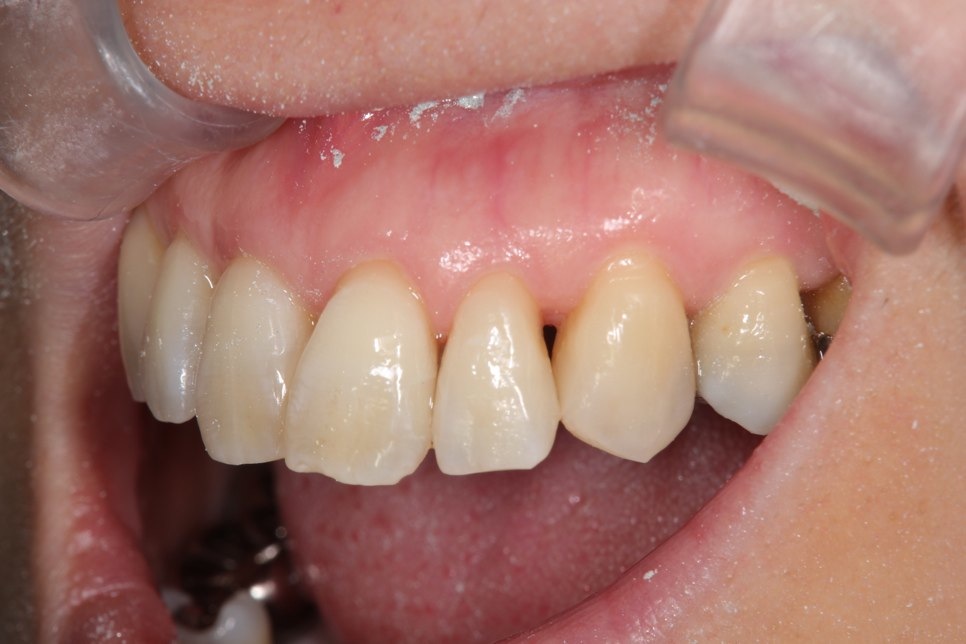

両奥に白い詰め物で治療してありますが、詰め物の周りが茶色に着色しています。また、本来の歯の形とはずいぶん違うみたいです。奥歯で噛んだ感じに違和感があるとの事でしたので、治療致しました。本来歯が持っている形をお口の中で作って行きます。

治療後です。どこを治療したのかわからないくらい『自然の歯』の様にできました。噛む時の違和感もなくなり、硬い物でも噛める様になりました。

左右奥歯のダイレクトボンディング

費用5万円×2本

リスクとして欠ける可能性がある(修復可能)。